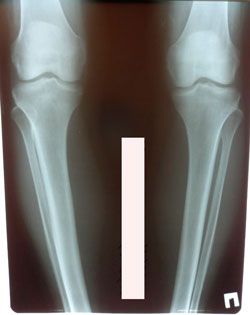

Исходник - 44 года.

Дата операции - 21.21.2021

image-22-01-21-05-17-7.jpg

image-22-01-21-05-17.jpg